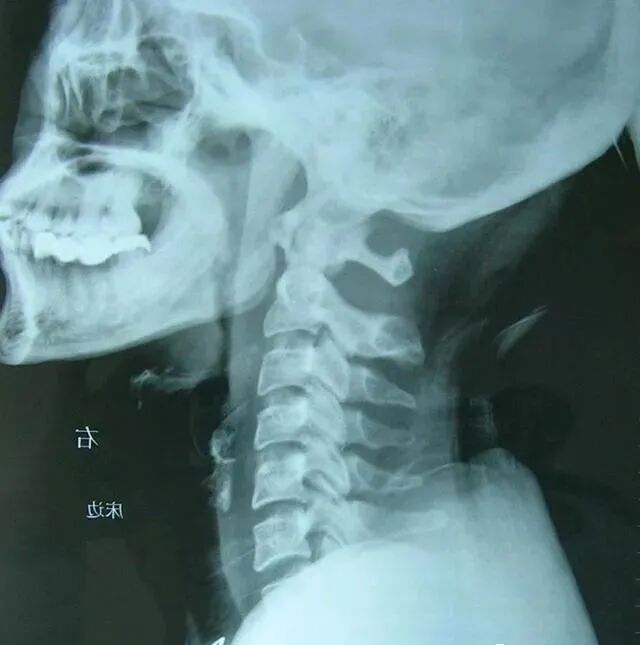

3.影像学检查:颈椎X线,颅骨或颈椎的CT或MRI扫描,以除外其他疾病。

图片